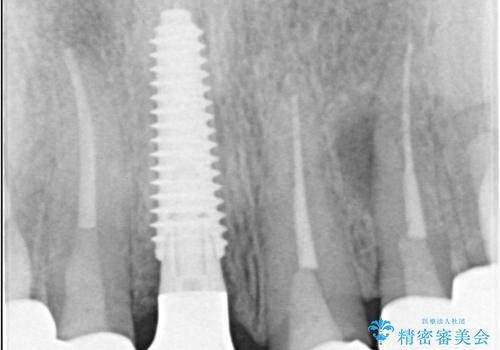

- 前歯の痛みと破折を主訴にご来院されました。精密な診査の結果、歯の根元までひび割れが進行し、保存が困難であると診断。見た目にも関わる前歯を失うことへの患者様の不安を考慮し、抜歯と同時にインプラントを埋入する抜歯即時埋入インプラントによる治療計画を立案しました。これにより、歯がない期間を最小限に抑え、治療期間と身体への負担を軽減しながら、審美性の高い新しい歯を獲得することを目指します。

今回の治療では、まず原因となっていた前歯を慎重に抜歯し、その直後にインプラントを埋入しました。抜歯即時埋入は、歯を失うのとほぼ同時に新しい歯の土台を確保できるため、骨の吸収を防ぎ、仕上がりの美しさを保つ上で非常に有効です。また、治療当日に仮歯を装着することで、歯がない期間をなくし、患者様の精神的なご負担にも配慮しました。最終的に、周囲の歯と調和したオーダーメイドのセラミッククラウンを装着。機能性だけでなく、天然歯と見分けがつかないほどの自然で美しい前歯を取り戻していただけました。